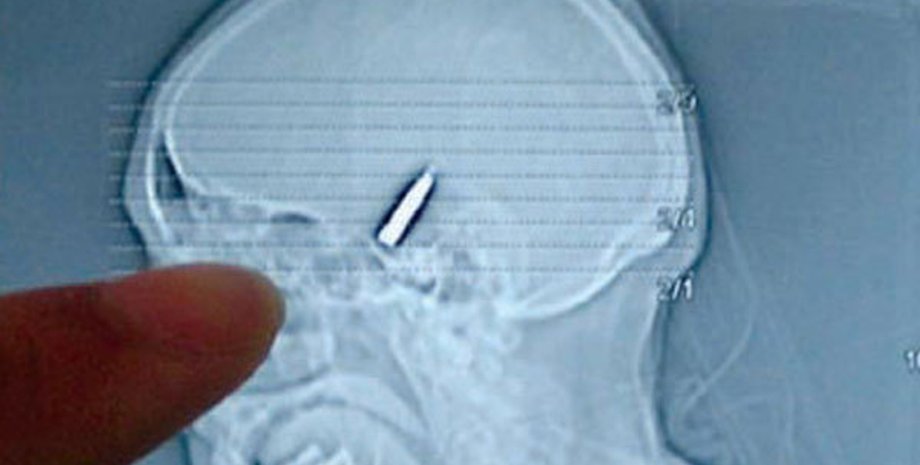

Уильям Лоулис Пэйс жил с пулей в голове 95 лет, передает Интерфакс.

Он получил ранение еще в 1917 году во время игры со старшим братом, который случайно ранил его из отцовской винтовки 22 калибра (5,6 миллиметра). Пуля застряла в голове мальчика.

Врачи штата Техас приняли решение не извлекать хирургическим путем пулю из головы Пэйса, поскольку опасались повреждений мозга в ходе операции.